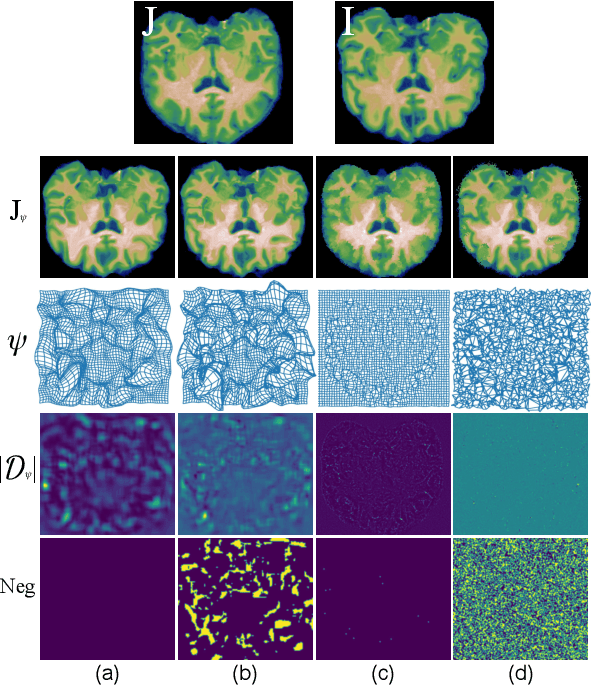

Abstract:Longitudinal assessment of brain atrophy, particularly in the hippocampus, is a well-studied biomarker for neurodegenerative diseases, such as Alzheimer's disease (AD). In clinical trials, estimation of brain progressive rates can be applied to track therapeutic efficacy of disease modifying treatments. However, most state-of-the-art measurements calculate changes directly by segmentation and/or deformable registration of MRI images, and may misreport head motion or MRI artifacts as neurodegeneration, impacting their accuracy. In our previous study, we developed a deep learning method DeepAtrophy that uses a convolutional neural network to quantify differences between longitudinal MRI scan pairs that are associated with time. DeepAtrophy has high accuracy in inferring temporal information from longitudinal MRI scans, such as temporal order or relative inter-scan interval. DeepAtrophy also provides an overall atrophy score that was shown to perform well as a potential biomarker of disease progression and treatment efficacy. However, DeepAtrophy is not interpretable, and it is unclear what changes in the MRI contribute to progression measurements. In this paper, we propose Regional Deep Atrophy (RDA), which combines the temporal inference approach from DeepAtrophy with a deformable registration neural network and attention mechanism that highlights regions in the MRI image where longitudinal changes are contributing to temporal inference. RDA has similar prediction accuracy as DeepAtrophy, but its additional interpretability makes it more acceptable for use in clinical settings, and may lead to more sensitive biomarkers for disease monitoring in clinical trials of early AD.